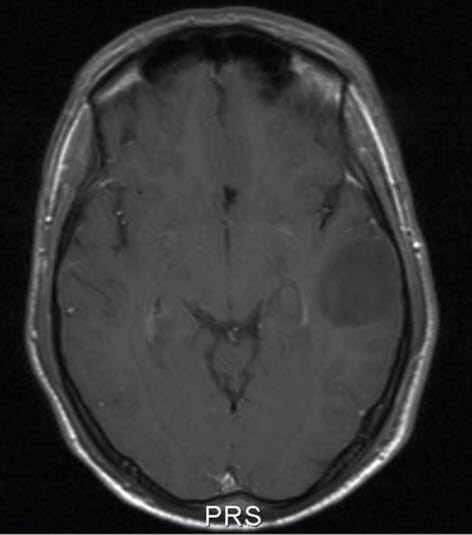

Lavgradig astrocytom, aksialt snitt

lavgradig astrocytom who grad ii 1

Lavgradig astrocytom WHO grad II

Gjengitt med tillatelse av Radiologisk avdeling, Universitetssykehuset Nord-Norge